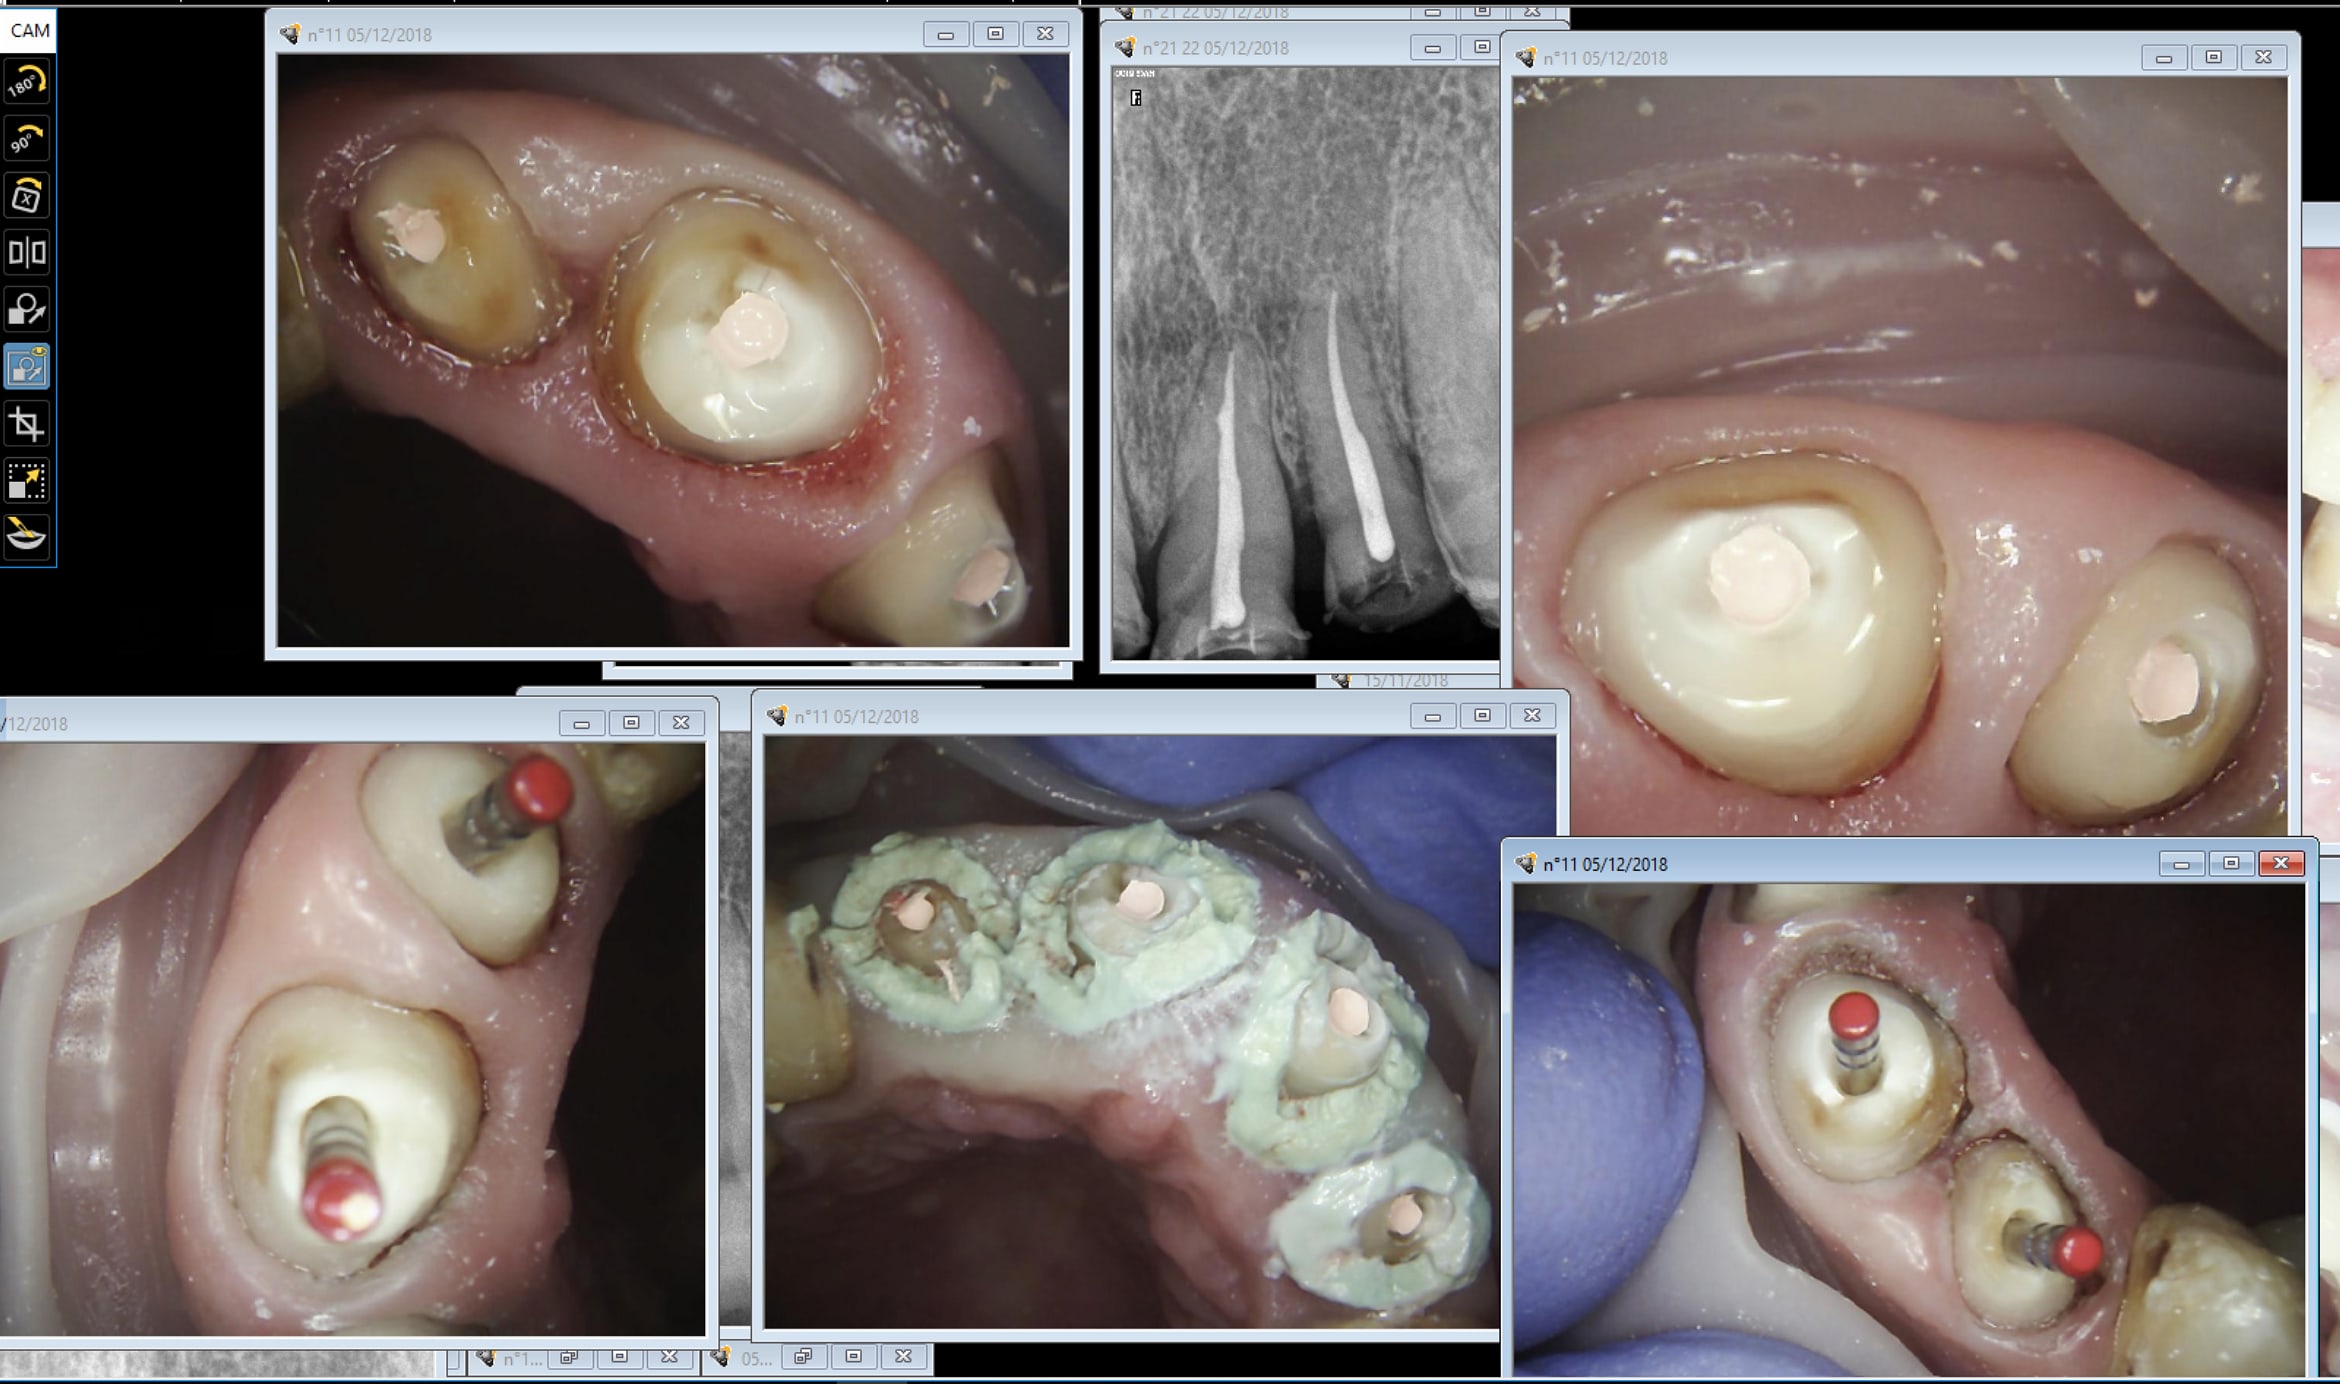

Faut essayer des cas plus délicats. presque one shot ( légère bascule du du bas) . Pour le haut commentaire : c'est mon 3 ième appareil jamais été aussi à l'aise.

Empreinte des selles en occlusion. Etape qu'on aurait pu faire à l'essayage des armatures.